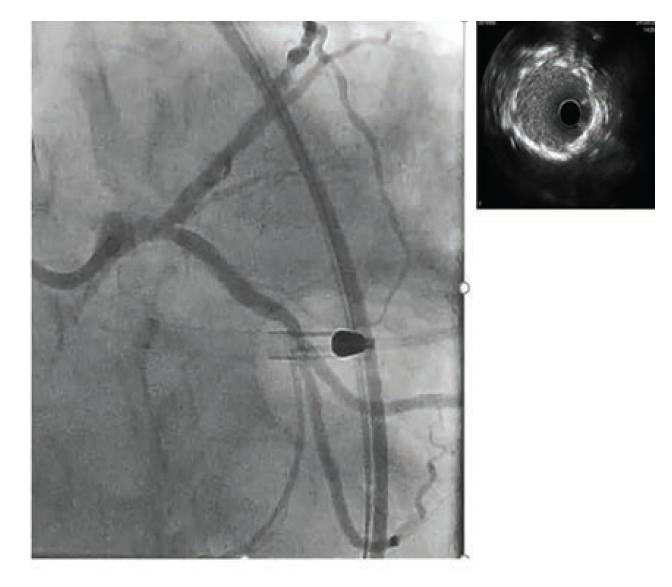

Given angiographic severe calcifications and the potential need for atherectomy, we opted to use Opticross HD intravascular ultrasound (IVUS) (Boston Scientific) for a better qualitative assessment of the lesion.

In order to facilitate delivery of the IVUS catheter, a 1.5 mm RX Takeru™ PTCA Balloon Dilatation Catheter (Terumo Interventional Systems) was used to predilate the ostium of the LCx and LAD, respectively. IVUS demonstrated dense calcification at the ostial LCx and LAD. However, the LCx calcium was found to be fractured and extended to less than <180 degrees, while the LAD calcification was severe and concentric at ~320 degrees (Figure 2).